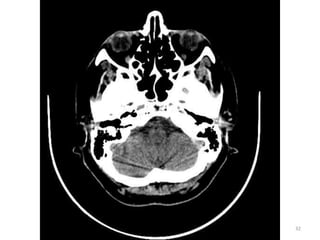

1. CORPO CALOSO

2. CORNO ANTERIOR

DO VENTRÍCULO

LATERAL D

3. FISSURA DE SILVYUS 4. NÚCLEO

LENTICULADO

5. TERCEIRO

VENTRÍCULO

6. SEIO SAGITAL SUPERIOR

1

2

3

4 5

6